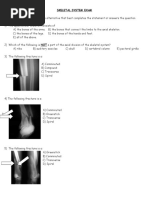

Label the bones